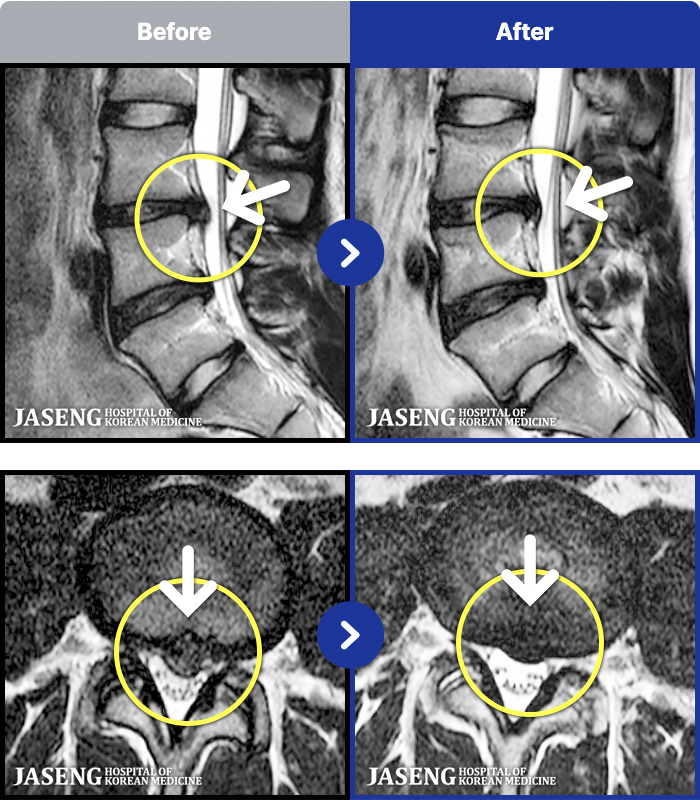

1,287 MRI ũ ʸ Ȯϼ.